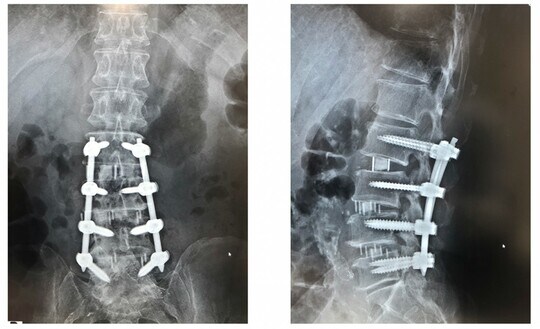

椎骨と椎骨のあいだにずれや不安定性が生じた場合は、椎骨間を固定する必要があります。そこで、お腹の横から侵入して大腰筋を裂き、椎間板のあいだに少し高めの補強材(ケージ)を入れて、椎体間を広げることにより間接的に脊柱管の狭窄を広げることができるのです。その後、医療用のインプラント(スクリュウやロッド)で固定します。

こうして、1度目の手術が無事に終了。筆者は、もし手術後にまだ下肢のしびれが残っていたら、神経の圧迫を解除する手術を追加しようと考えていましたが、Tさんの場合、1度目の手術で痛みやしびれが大きく改善されたためその予定を変更し、2度目は背中側から金属で固定するという手術のみを行いました。